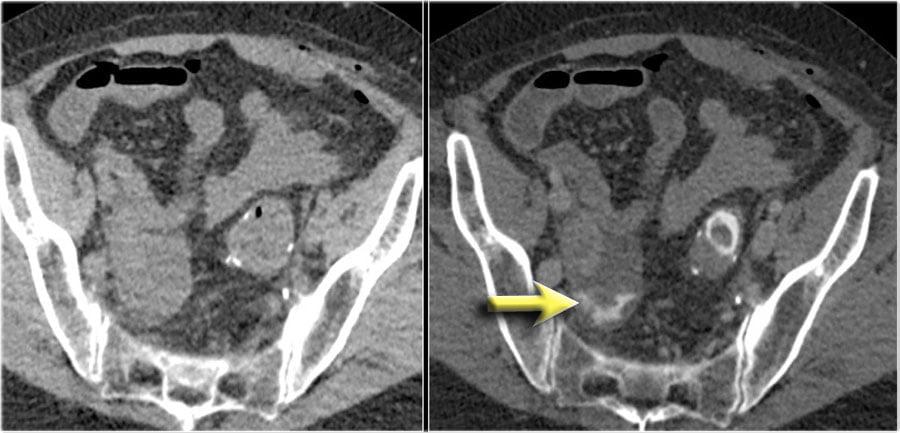

Here a patient with an anastomosis in the lower abdomen after resection of a sigmoid carcinoma.

Compare the NECT without oral or rectal contrast on the left with the images on the right after rectal contrast.

There is no doubt, that contrast in the fluid collection in the right lower abdomen is the result of leakage from the bowel (arrow).

Bệnh nhân bị rò mối nối sau mổ ung thư đại tràng sigma.

Hình bên trái không bơm thuốc so sánh với hình bên phải có bơm thuốc đường trực tràng.

Không còn nghi ngờ gì nữa, có thuốc cản quang trong vùng tụ dịch ở vùng bụng dưới bên phải là kết quả của sự rò từ ruột (mũi tên).